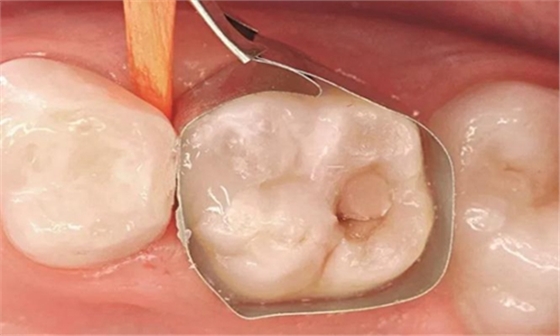

圖4:64號乳牙去腐后,放置一個T型成行片和一個木楔

圖5:用Prime&Bond NT (Dentsply De Trey) 處理窩洞,作用時間為20秒,然后輕吹至少5秒并光固化10秒

圖6:在取下成行片之前用復(fù)合體(Dyract, Dentsply De Trey)填充窩洞并固化

圖7:對64號乳牙的近中面洞充填并完成調(diào)磨。然后重新充填面的單個窩洞